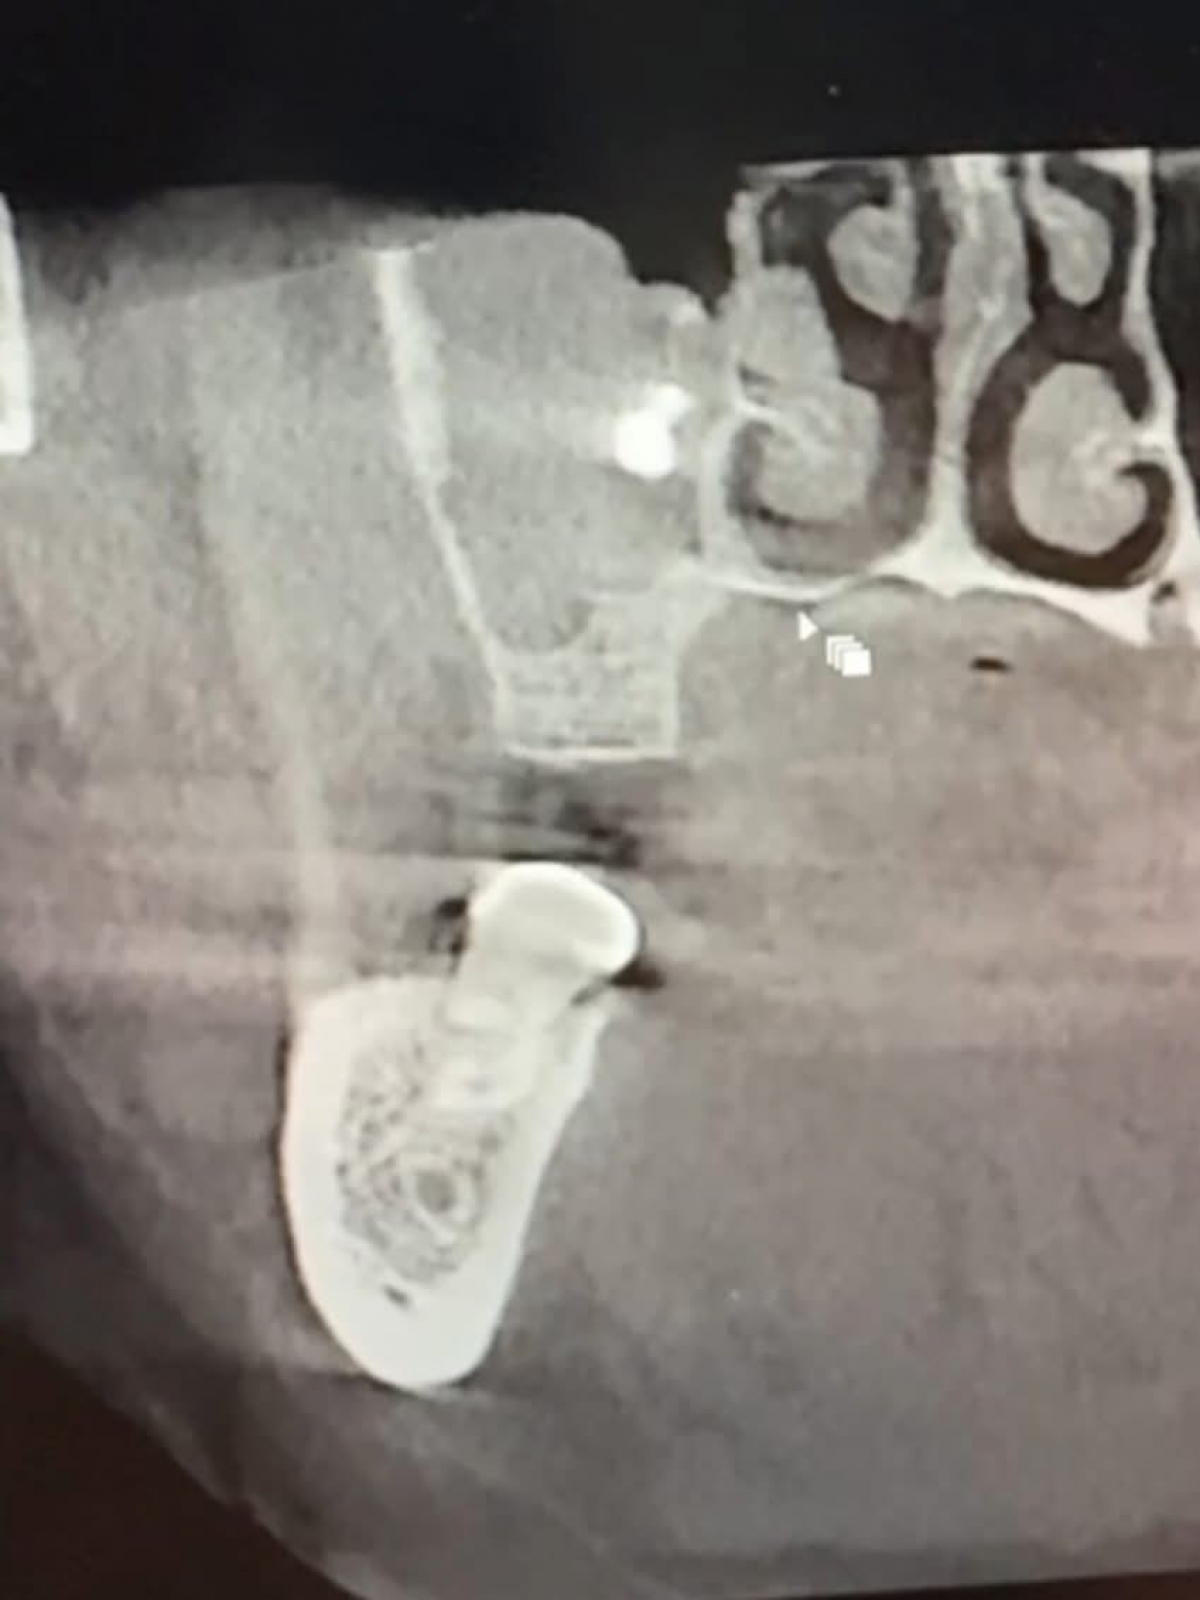

Під час прийому у стоматолога було діагностовано наявність стороннього тіла у верхньощелепній пазусі.

Після направлення до Володимирського

ТМО лікарі-отоларингологи оперативно та успішно видалили стороннє тіло. Процедуру проведено без ускладнень, пацієнт почувається задовільно.